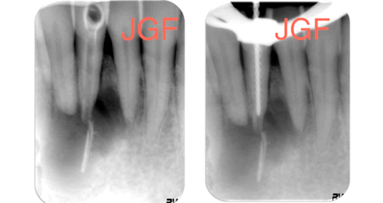

Figura 1. Situación de partida en el diente 35.

Figura 2. Situación de partida: pérdida acusada de sustancia en el diente 35 en la zona visible.

En el presente caso, el paciente se presentó con una pérdida acusada de sustancia en el diente 35 (Figuras 1-3). La preparación a modo de abrazadera o ferrule necesaria para una reconstrucción de espiga colada habría debilitado aún más la sustancia dental. Teniendo en cuenta la carga prevista sobre el muñón, se consideró insuficiente un anclaje de espiga puramente retentivo conforme al modelo tradicional. Así pues, en este caso se optó por la reconstrucción de espiga directa utilizando la técnica adhesiva. Además, la utilización de sistemas basados en la técnica adhesiva posibilita un procedimiento mínimamente invasivo, que conserva la sustancia dental y la aprovecha para la unión adhesiva.